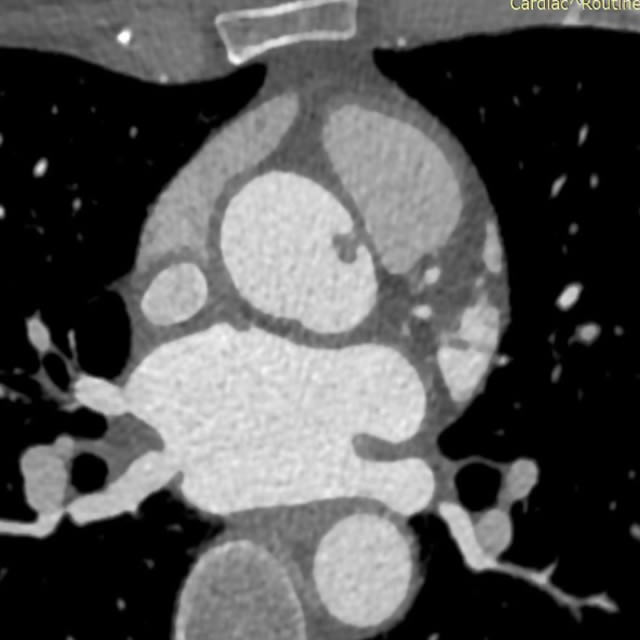

Categorical courses, offering AMA PRA Category 1 Credits™, range from two to five days within the four-week course and provide radiologic-pathologic correlation for both radiology residents and practicing radiologists to show how the underlying pathology of a lesion relates to its imaging appearance.

The mission of these courses is to enable participants to utilize knowledge of how radiology and pathology correlate to improve their diagnostic accuracy in identifying specific diseases, their treatment and potential complications.